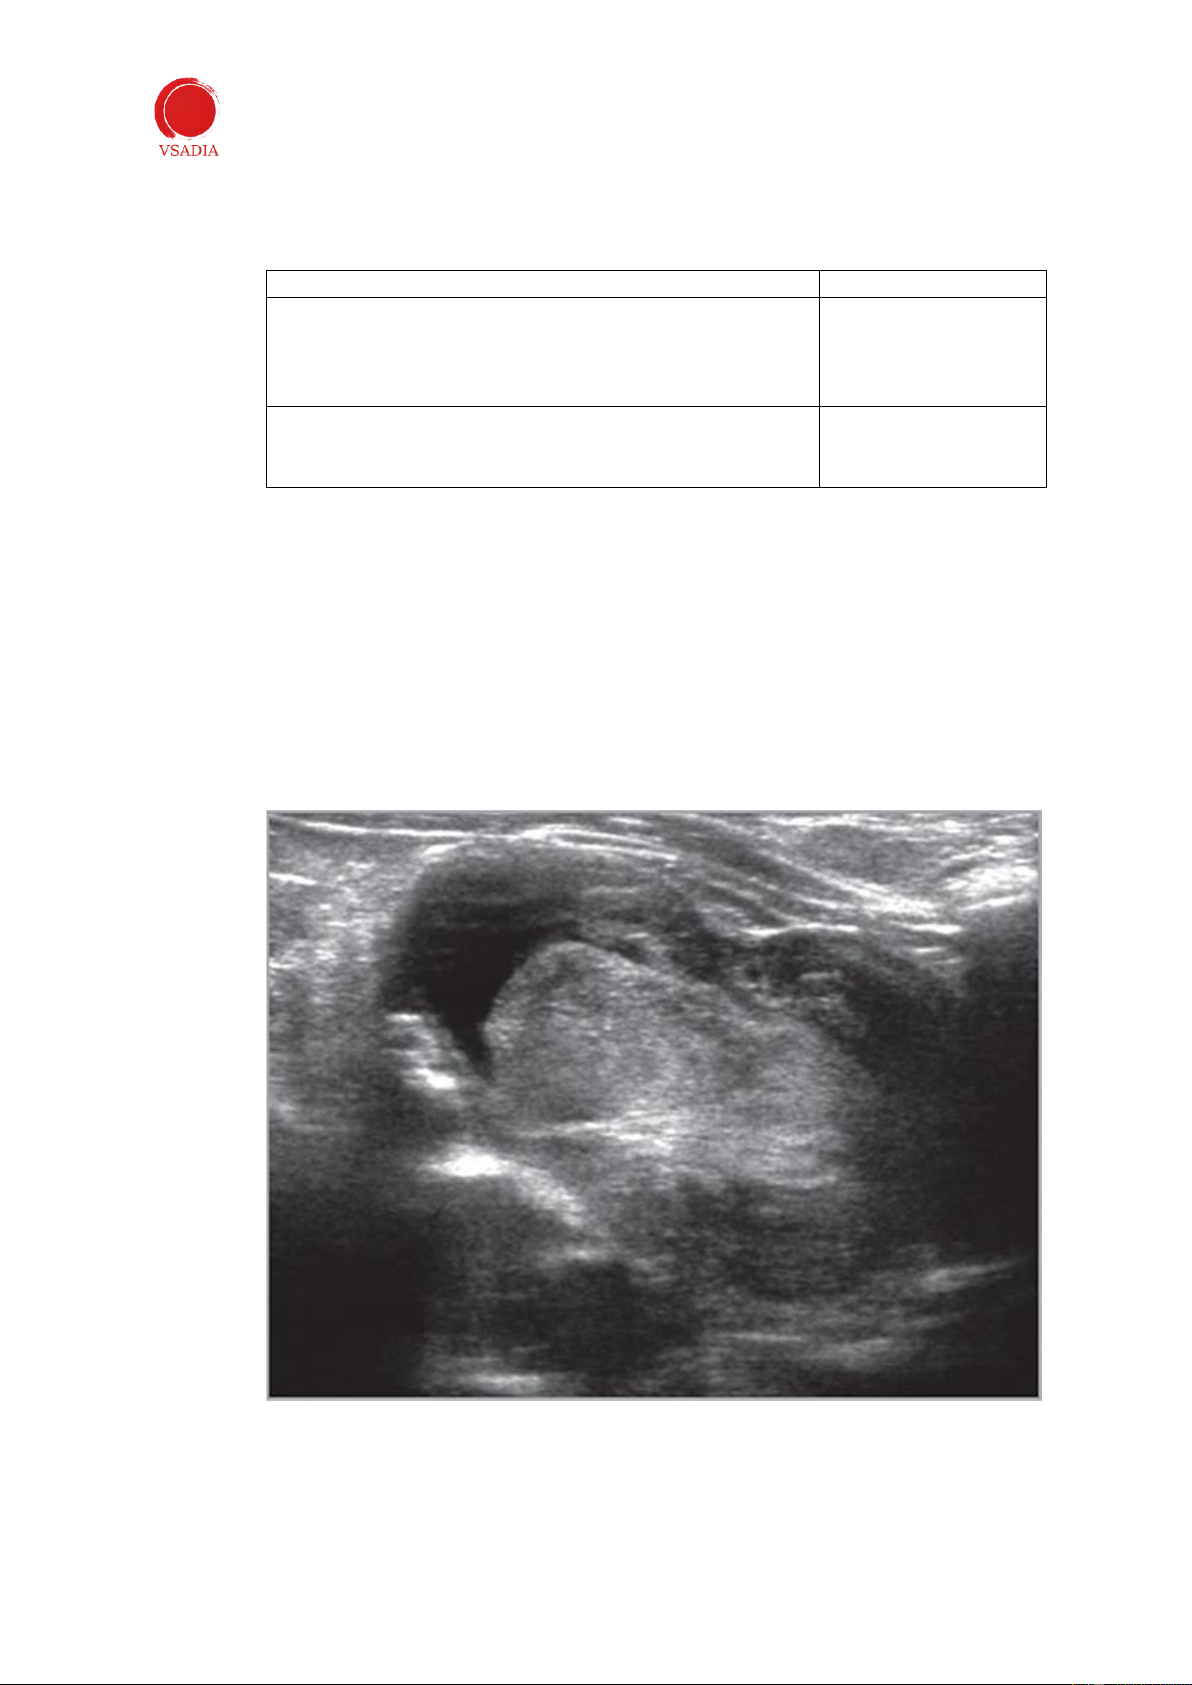

Xác định bàng quang và đại tràng rồi trượt đầu dò về phía sau (Hình 4). Tử cung (hoặc

gốc tử cung nếu con cái đã triệt sản) nằm giữa bàng quang và kết tràng (Hình 5 và 6).

Hình 4: Sau khi xác định bàng quang và kết tràng, đầu dò được di chuyển về phía sau để xác định tử cung hoặc

gốc tử cung nằm giữa bàng quang và kết tràng.

Hình 5: Hình ảnh cắt ngang của tử cung . Thân tử cung giảm âm được nhìn thấy giữa bàng quang và đại tràng.